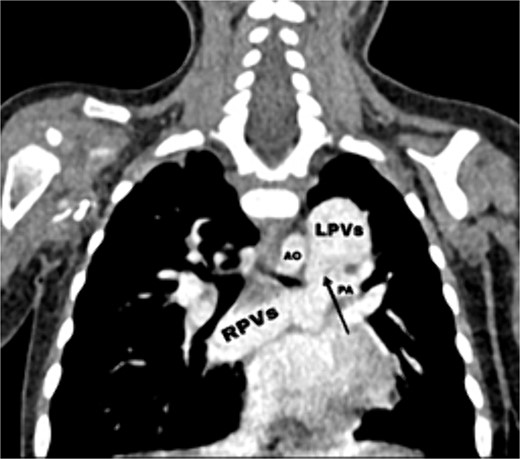

CT scan showing the right pulmonary veins (RPVs) and left pulmonary veins (LPVs) join all together posterior to the left atrium (LA) and pulmonary artery (PA), also showing the stenosis within the venous confluence between the drain of the right pulmonary veins and the drain of the left pulmonary veins.